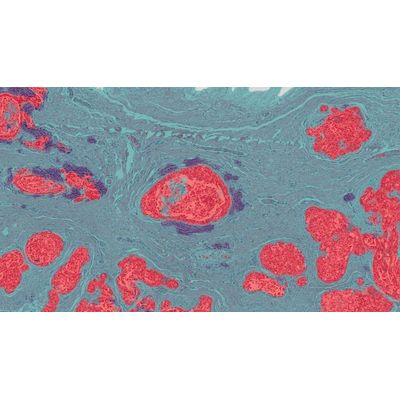

For this application, MiniNet was used to separate tumor from lymphocytic clusters and stroma in and H&E stained breast cancer tissue. MiniNet is a shallow neural network, but it works well on routine classification tasks and may be used as an alternative to HALO tissue classifier (random forest) in some instances. It is also recommended for quick proof-of-concept studies before moving over to the more data and time intensive VGG and DenseNet networks. Open full-sized image.